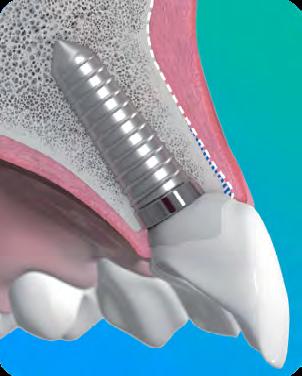

Immediate Implant Placement: 5 Steps to Predictable Esthetic Outcomes

Predictable Immediate Implant Placement Starts with Biology

When biologic principles are respected, esthetic-zone outcomes become consistent and stable.

Immediate implant placement becomes predictable when biology and protocol work together.